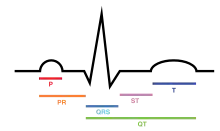

Basic representation of cardiac electrical conduction | |

An electrocardiogram is a recording of the electrical activity of the heart.

SA node: P wave

Under normal conditions, electrical activity is spontaneously generated by the SA node, the cardiac pacemaker. This electrical impulse is propagated throughout the right atrium, and through Bachmann's bundle to the left atrium, stimulating the myocardium of the atria to contract. The conduction of the electrical impulses throughout the atria is seen on the ECG as the P wave.[5][7]

AV node and bundles: PR interval

The AV node functions as a critical delay in the conduction system. Without this delay, the atria and ventricles would contract at the same time, and blood wouldn't flow effectively from the atria to the ventricles. The delay in the AV node forms much of the PR segment on the ECG, and part of atrial repolarization can be represented by the PR segment.

Purkinje fibers/ventricular myocardium: QRS complex

The spread of electrical activity through the ventricular myocardium produces the QRS complex on the ECG.

Atrial repolarization occurs and is masked during the QRS complex by ventricular depolarization on the ECG.

Ventricular repolarization

The last event of the cycle is the repolarization of the ventricles. It is the restoring of the resting state. In the ECG, repolarization includes the J point, ST segment, and T and U waves.[9] The transthoracically measured PQRS portion of an electrocardiogram is chiefly influenced by the sympathetic nervous system. The T (and occasionally U) waves are chiefly influenced by the parasympathetic nervous system guided by integrated brainstem control from the vagus nerve and the thoracic spinal accessory ganglia.

An impulse (action potential) that originates from the SA node at a relative rate of 60-100 bpm is known as a normal sinus rhythm. If SA nodal impulses occur at a rate less than 60 bpm, the heart rhythm is known as sinus bradycardia. If SA nodal impulses occur at a rate exceeding 100bpm, the consequent rapid heart rate is sinus tachycardia. These conditions are not necessarily bad symptoms, however. Trained athletes, for example, usually show heart rates slower than 60bpm when not exercising. If the SA node fails to initialize, the AV junction can take over as the main pacemaker of the heart. The AV junction consists of the AV node, the bundle of His, and the surrounding area; it has a regular rate of 40 to 60bpm. These "junctional" rhythms are characterized by a missing or inverted P wave. If both the SA node and the AV junction fail to initialize the electrical impulse, the ventricles can fire the electrical impulses themselves at a rate of 20 to 40 bpm and will have a QRS complex of greater than 120 ms. This is necessary for the heart to be in good function.